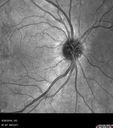

Proliferative Diabetic Retinopathy NVD left eye and NVE right eye - Ultrawide field FA

40 year old woman with diabets Decreased Vision OS. Quality: "cloudy". Associated Symptoms: floaters OS. "like a spider web". Duration of Problem: 2 weeks

VA 2025 OD 20/50 OS. Severe NVD OS required PRP injections and ultimately PPV x 2. Vision 6 months later was 20/25 but she is developing more of a cataract. The right eye is doing well with PRP

PDR NVD left eye and NVE right eye595 views41 year old diabetic woman with PDR in both eyes. High risk in the left eye. She had PRP, Avastin, and vitrectomy x 2 in the left eye with final vision of 20/25. The right eye had eventually PRP laser     (0 votes)